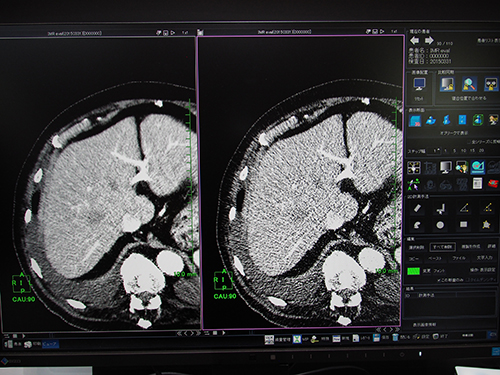

統計的CT画像ノイズ低減機能(W.I.P.)は,thin sliceのボリュームデータに適応した画像ノイズ低減機能。各ピクセルの三次元的近傍から推定されたノイズの統計量を基にノイズパターンを解析し,元の画像からノイズを差分することで画像ノイズの低減を行う。レトロスペクティブにノイズを低減できるため,thin slice画像再構成などの場合に生じる線量不足による画像ノイズを低減することができる。画像ノイズ(SD)測定では,線量を約1/4に低減しても同等の画質を得られるという。ノイズを低減することでコントラストが向上し,物体抽出の精度が上がるため,MIP画像やVR画像などで血管をより明瞭に描出することが可能になる。ワークステーションによる画像解析の精度は元画像のクオリティに依存するため,ノイズの少ない画像を得られることで,画像解析も容易になる。

レトロスペクティブにノイズを低減する統計的CT画像ノイズ低減機能(W.I.P.)

ノイズに埋もれた血管もノイズを低減することで観察可能

VR表示など,さまざまな表示法でノイズ低減効果が実感できる。